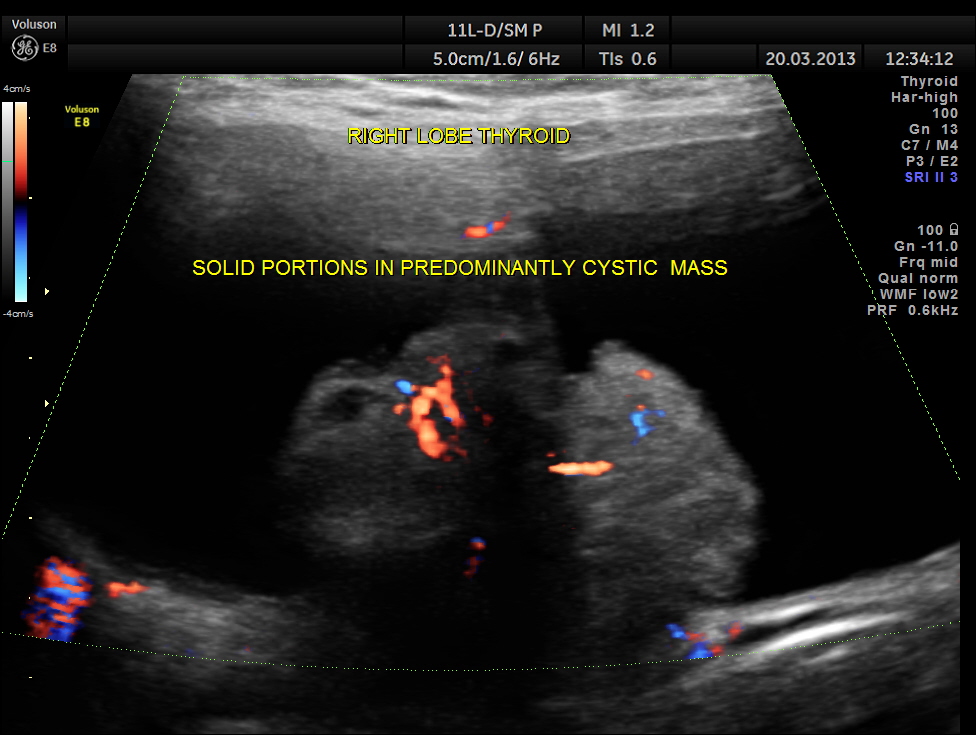

The right lobe of the thyroid was grossly enlarged , with predominantly cystic appearance , with eccentric solid tissue, with prominently increased vascularity in the solid portion.